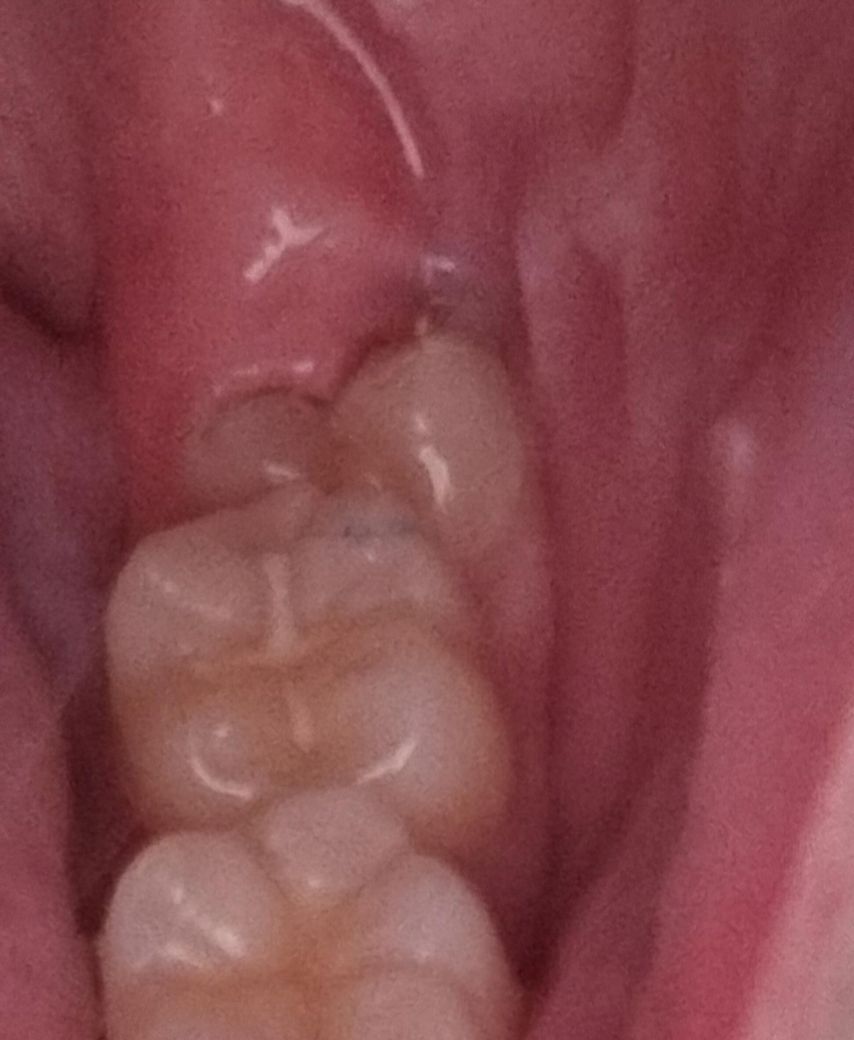

이거 반매복 사랑니 인가요? 뽑을때 무조건 잇몸 쨔야하나요?

잇몸 안 찢고 뽑울수는 없는거겠죠...?

전에 잇몸 째고 뽑았는데 마취풀리고 너무너무 아팠어서...ㅠㅠ 뽑으면 몇바늘 정도 꿰맬까요?ㅠㅠ

• 1번 째 사진

잇몸이 반정도 덮혀 잇어서 발치시 잇몸절개를 조금은 해야될것같습니다. 발치후에 한두바늘 정도 꿰매면 될것같습니다.

사랑니는 부분적으로 매복되어 있는 것으로 보입니다. 사랑니의 크기가 크지 않다면 잇몸을 절개하지 않고도 나올 수 있지만 잇몸을 절개하고 사랑니를 발치하는 것이 오히려 주변 조직의 손상을 줄일 수 있습니다. 자세한 확인을 위해서 치과에서 진료를 받아보는 것을 권해드립니다.

현재 일부분이 매복이되어 있는 상태로 잇몸을 절개하여 사랑니를 쪼개어 발치가 필요로 될 가능성이 높습니다.

잇몸을 절개 한 후에 발치를 해야할 것 같으며 꿰메는 횟수는 대략 2~3회 정도 예상됩니다.